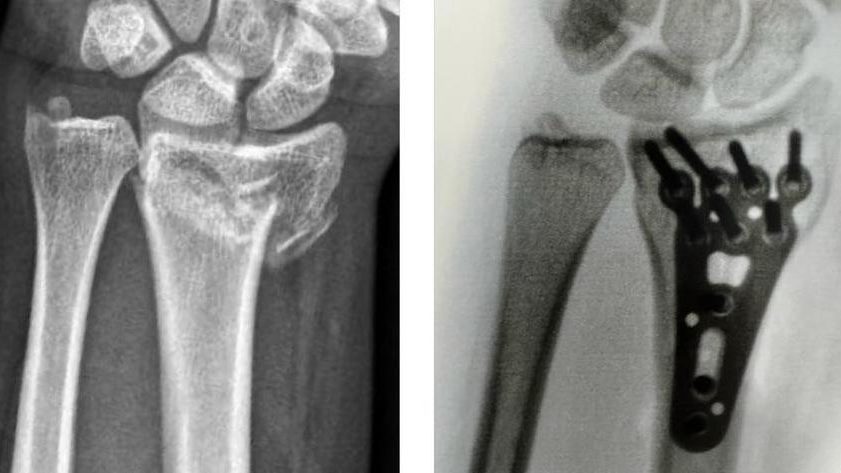

No caso de fraturas instáveis, ou com alta probabilidade de instabilidade, deve-se optar pelo tratamento cirúrgico, a fim de aumentar as chance de consolidação do osso em uma posição mais próxima do ideal possível. Para esse fim, utiliza-se materiais de síntese, as famosas placas e parafusos.

Exemplo de fratura da extremidade distal do rádio tratado com placa e parafusos